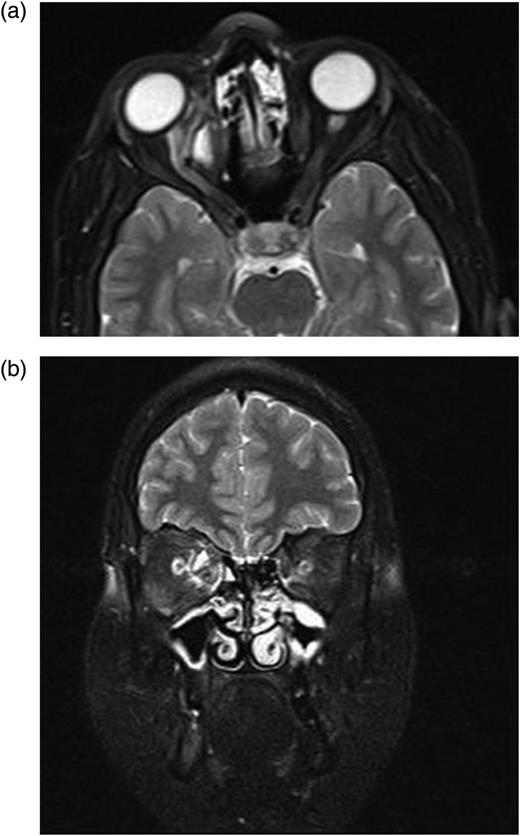

A complete blood cell count and serum laboratory values were normal without mild eosinophilia. Axial-coronal orbital magnetic resonance imaging (MRI) revealed a well-defined homogenous unilocular lesion in intraconal region of the right orbita which was hypointense on T1-weighted images and hyperintense on T2-weighted images after an intravenous injection of gadolinium-ethoxybenzyl-diethylenetriamine pentaacetic acid (Fig. 2a and b). The lesion was adjacent to optic nerve and medial rectus muscle and exerting pressure on the optic nerve and displacing optic nerve laterally. Approximate dimension of the lesion was 2 cm × 2 cm × 2 cm (Fig. 2a and b). Because it was difficult to distinguish hydatid cyst from other mass lesions of the orbita via MR, other mass lesions like neurocysticercosis, dermoid, lipodermoid, mucocele, encephalocele, inclusion cyst, teratoma, hematocele, schwannoma and paraganglioma were considered in the differential diagnosis of hydatid cyst.

(a and b) Axial-coronal orbital magnetic resonance imaging show the homogenous unilocular lesion that is adjacent to optic nerve and medial rectus muscle in the intraconal space and displacing optic nerve laterally.